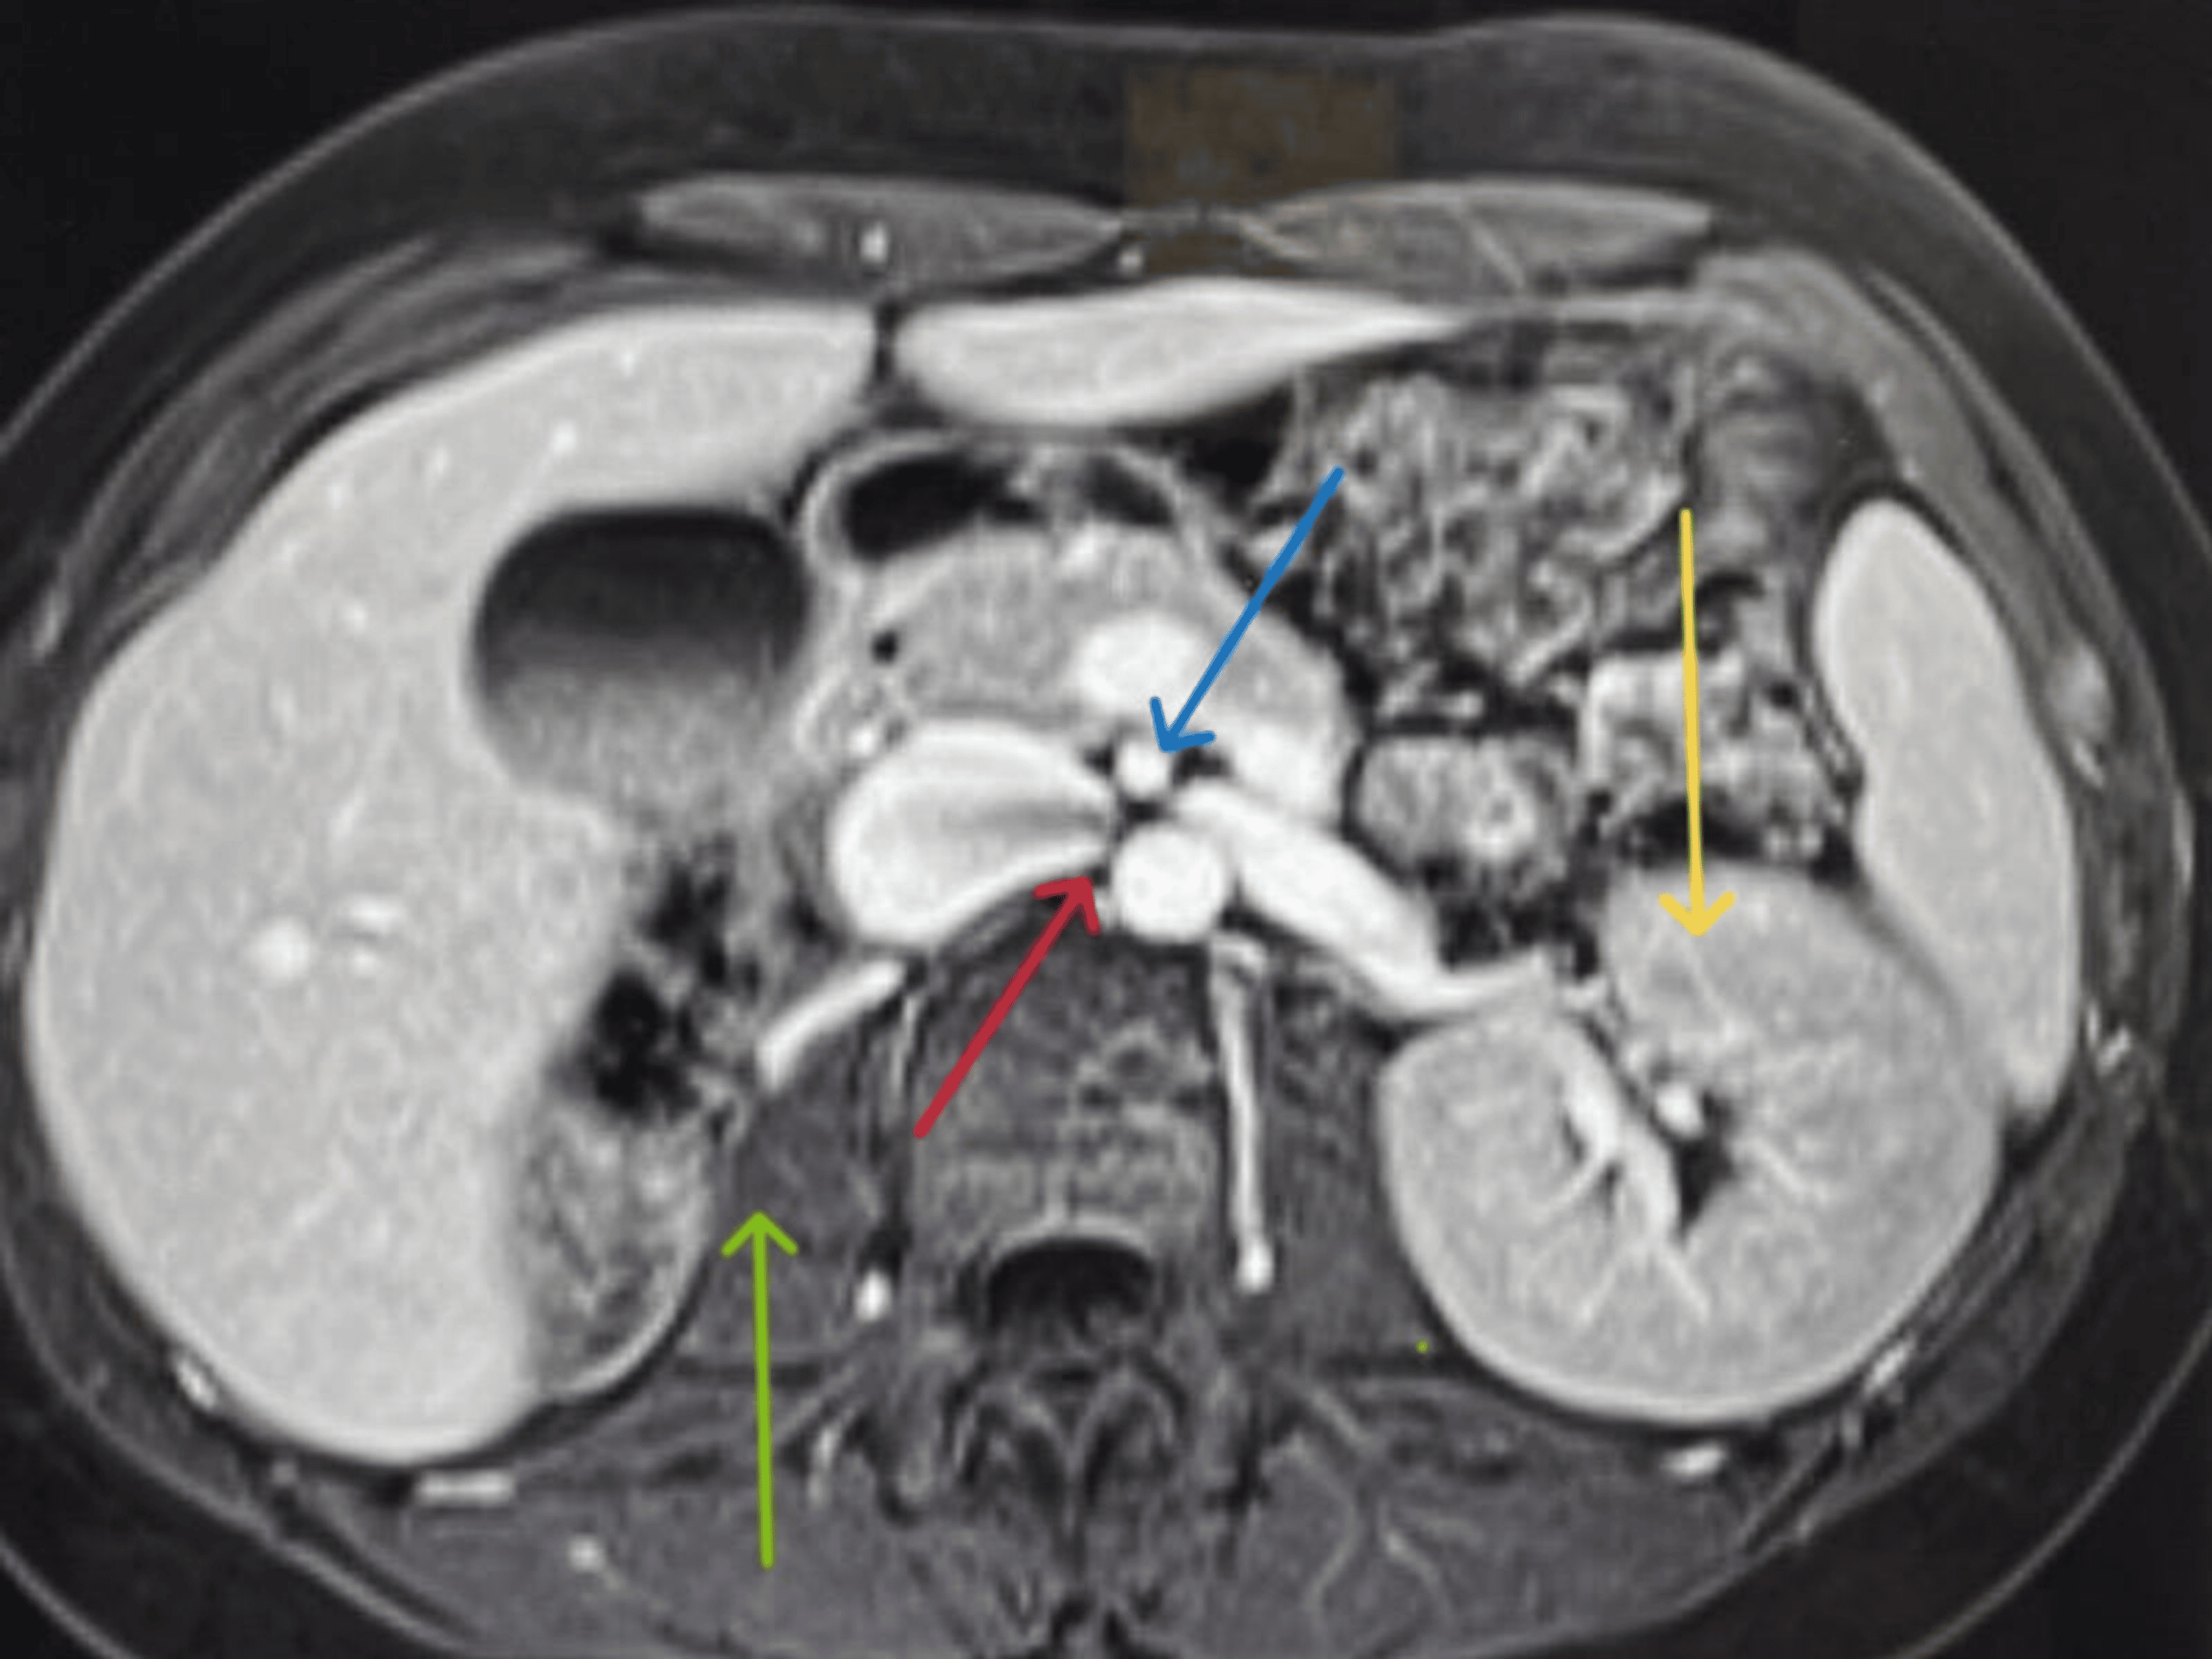

From radiopaedia.org